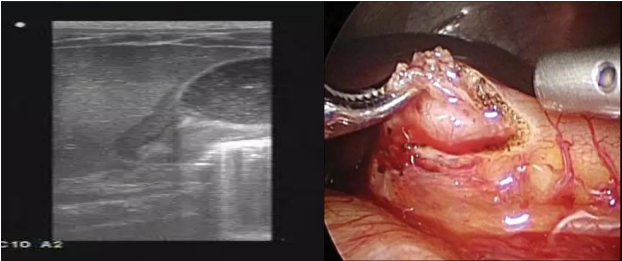

先天性肥厚性幽門狹窄的首發(fā)臨床癥狀為“嘔吐”,而且出生后大多沒有癥狀,2到3周后才出現(xiàn)嘔吐,嘔吐呈噴射性,并且越來越重,腹部檢查可見胃蠕動波,有的可以摸到腹部腫塊。過去先天性肥厚性幽門狹窄主要依靠X線確診,但是X線檢查,嬰兒不合作,易導致檢查失敗,近年來多采用超聲檢查,超聲可顯示幽門管長度、幽門肌厚度,還可了解胃的蠕動和排空情況,準確性較高,因此成為肥厚性幽門狹窄的診斷標準。

肥厚性幽門狹窄是嬰幼兒期最常見的必須進行外科手術(shù)治療的疾病,常采取腹腔鏡幽門環(huán)肌切開的手術(shù)方式,術(shù)后預后都很好,大多數(shù)病人在手術(shù)后1至2天可以恢復飲食并出院。